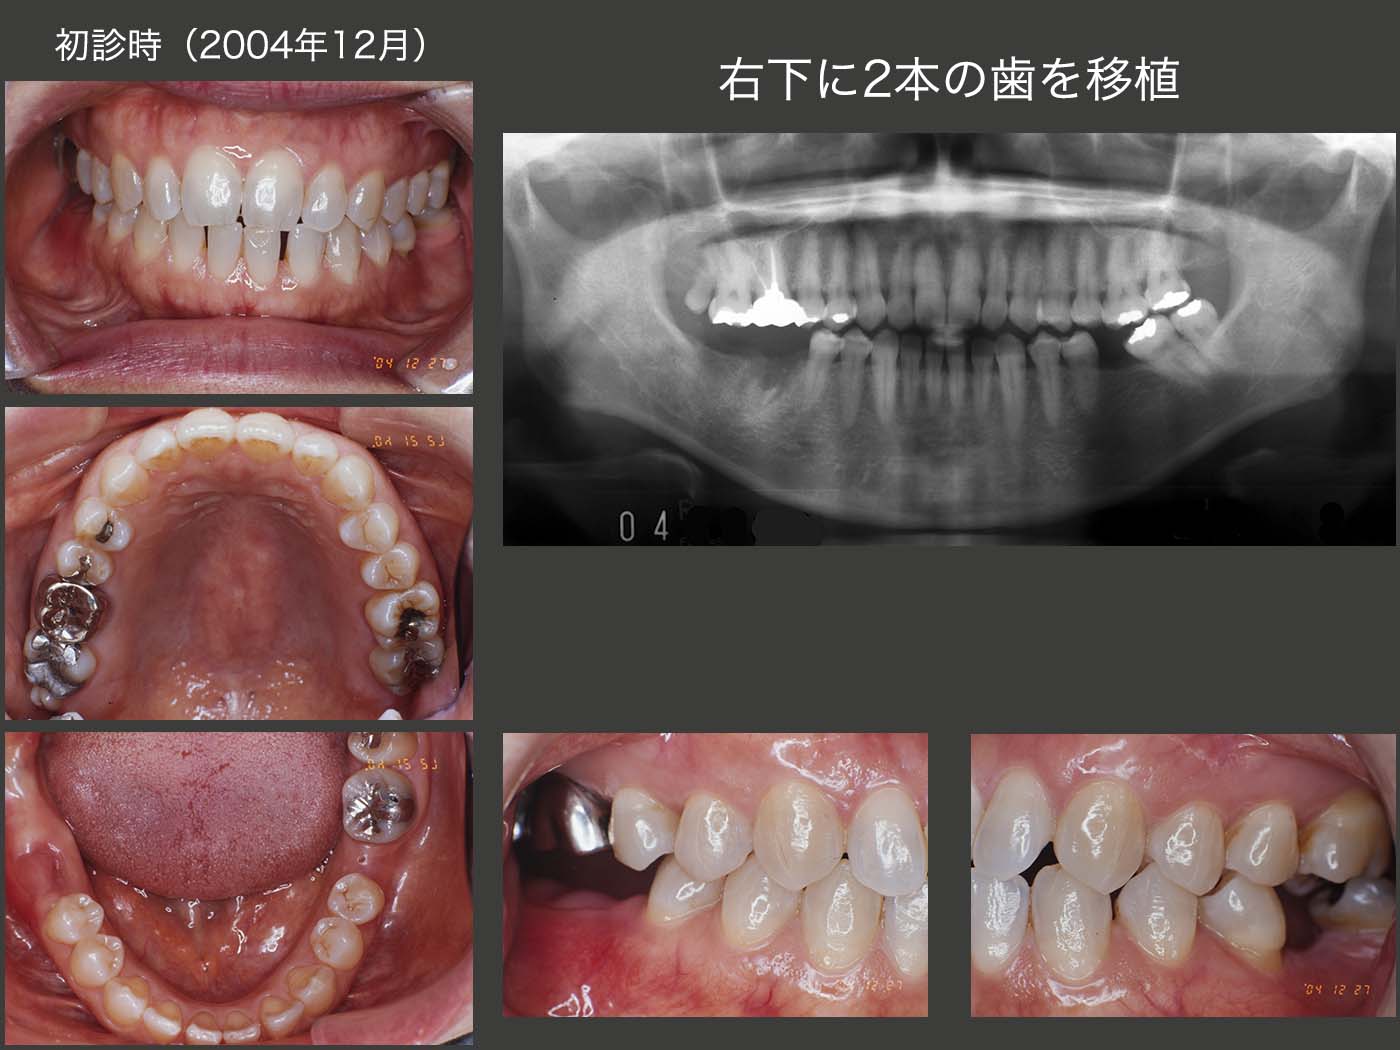

13.右下に2本の歯を移植

2004年12月初診,52歳の女性.主訴は,1ヵ月半前に右下を他院で抜歯したが,まだ痛みがあり,またあとの治療をどうしたらよいか悩んでいるとのこと.以前左下6を抜去後,放置したために左下7が近心傾斜していることから,左下8をドナー歯として右下に移植し,左下7をアップライトすれば,全体のバランスがとれることを説明し,同意を得た.また右上8も非機能歯であることから,この歯も一緒に移植することにした.